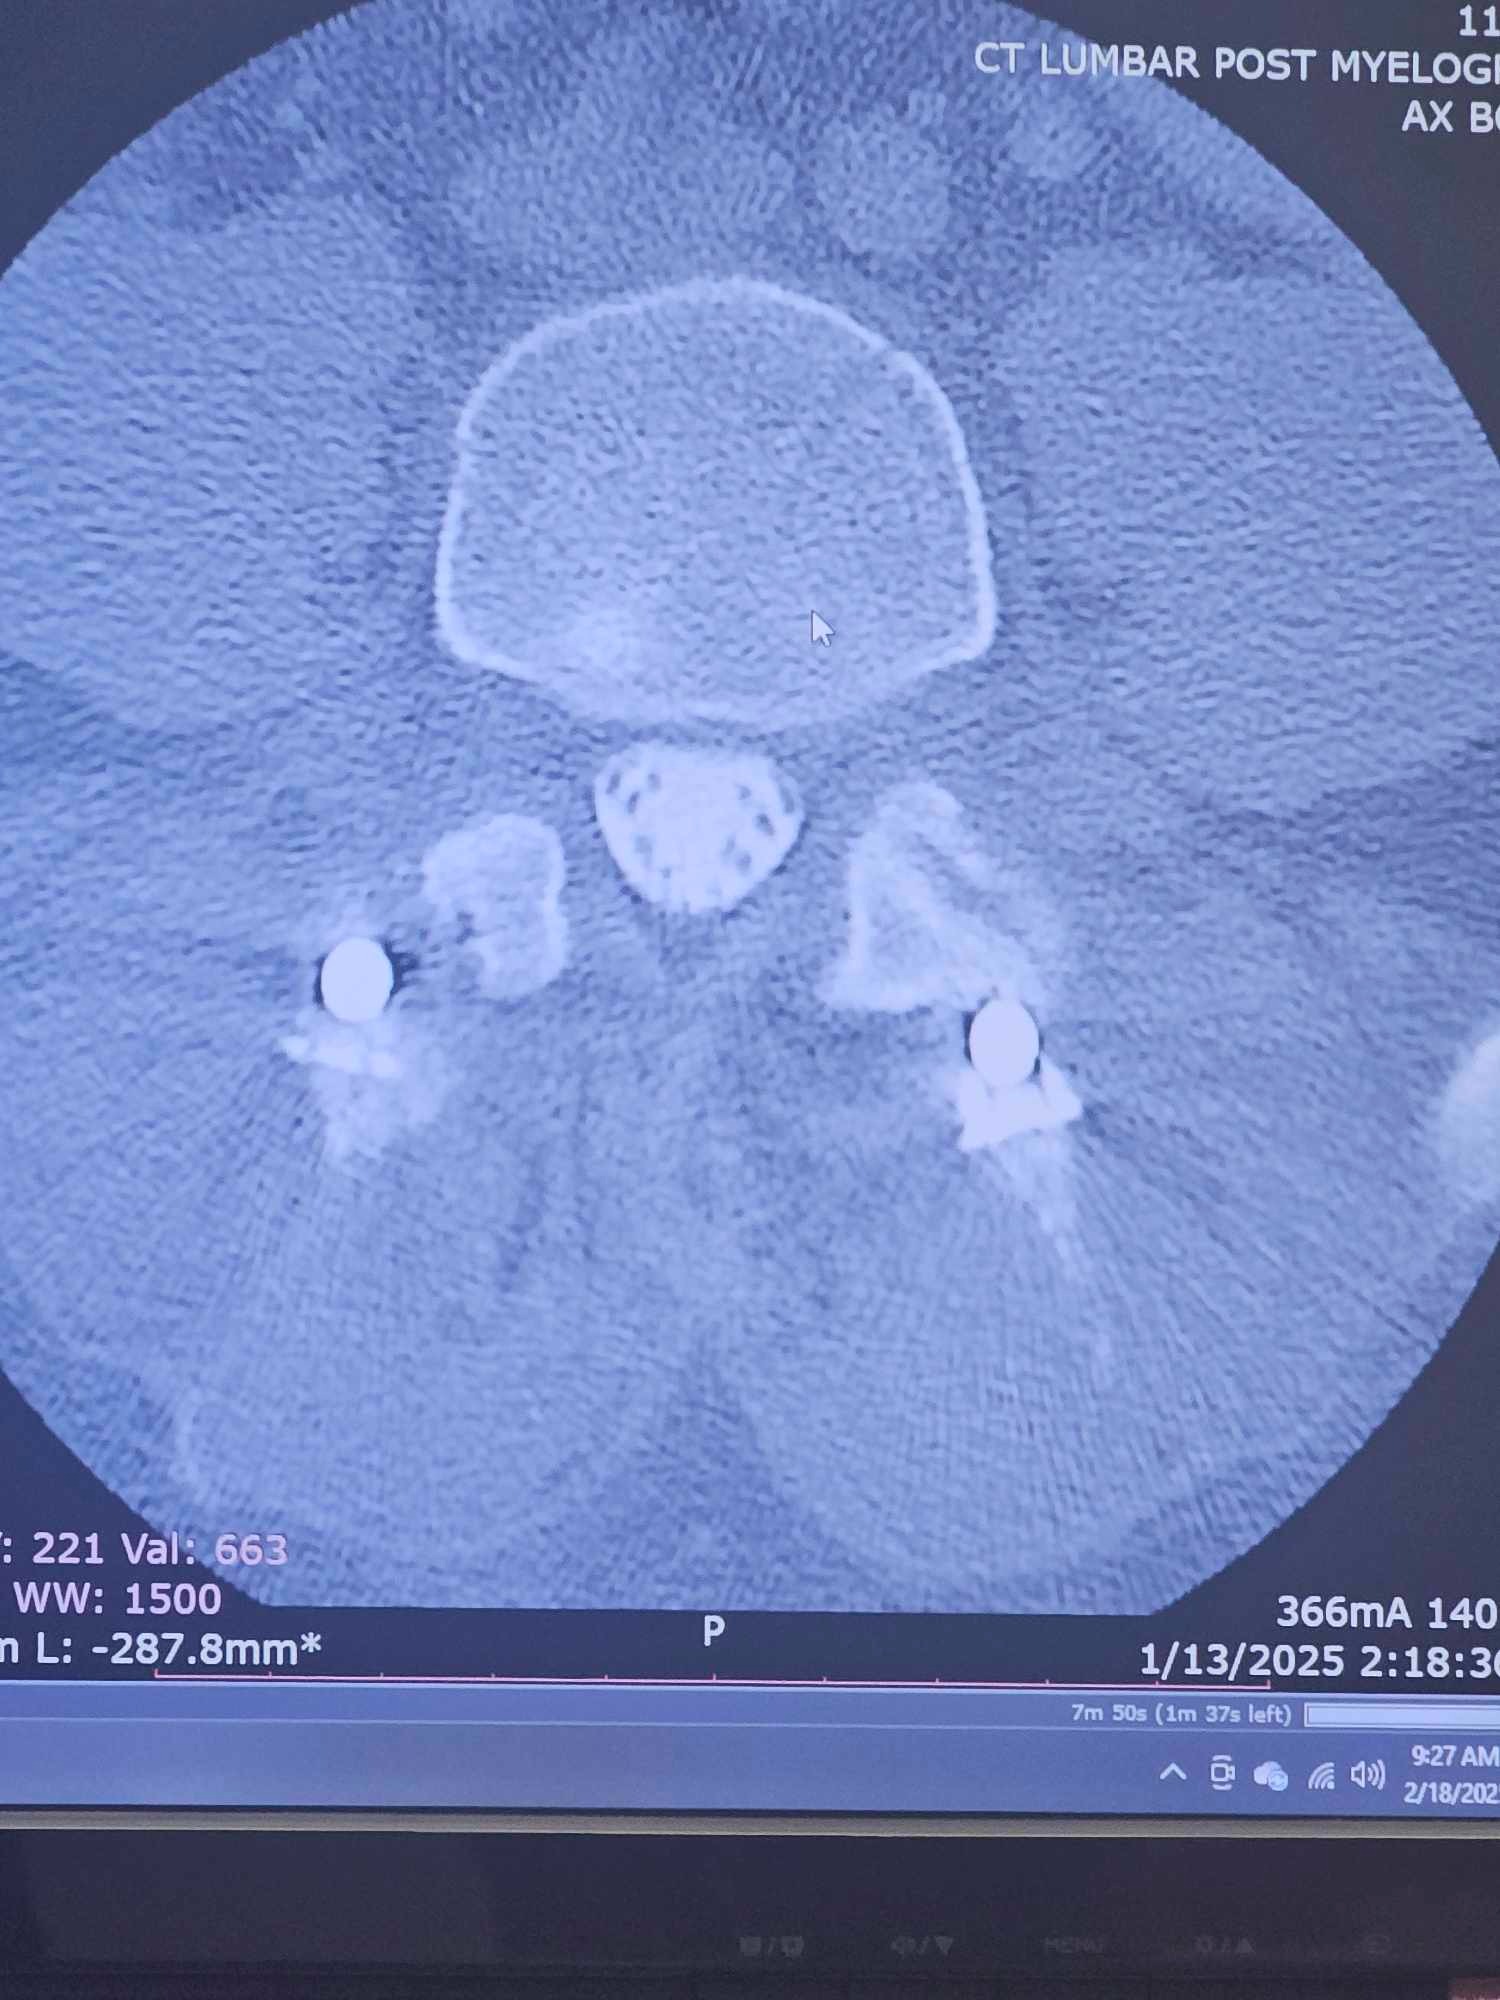

My name is Sonny Gentry. I was in a wreck 3 years ago at no fault of my own at 70 mph. As time passed by, my neck and lower back began to deteriorate. After waiting a very long time, I finally had surgery on July 15th, 2024, and that was a complete fail. I am only able to stand for 30 minutes at a time, and meds only help very little. Just really needing help with bills and meds as I am unable to work after all these years of working. Please feel in your heart to help. If CashApp $southerneuf81 or Venmo @sonny-gentry25 is better for you, then that's great too.